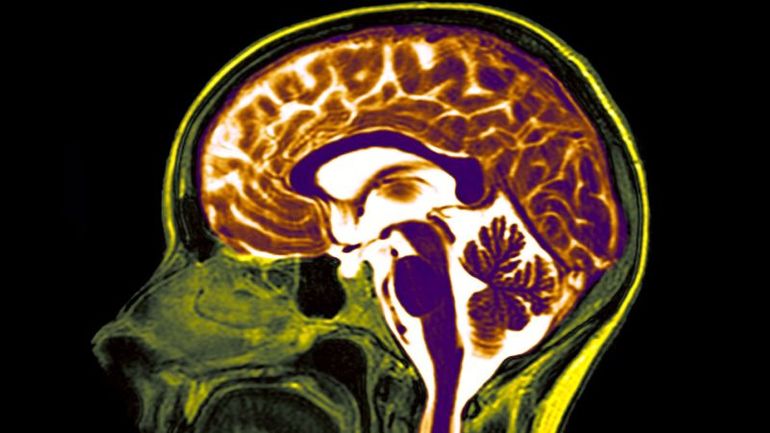

The world of neuroscience and technology has witnessed a remarkable intersection with the development of brain implants. These cutting-edge devices, also known as brain-computer interfaces, hold the potential to revolutionize the way individuals interact with technology and even overcome physical limitations. The concept of using thoughts to control devices such as computers and phones is no longer confined to science fiction, as researchers delve deeper into the realm of brain implants.

The functionality of brain implants involves the placement of devices on the brain's surface or deep within its intricate structure. These devices, equipped with electrodes, are designed to intercept and interpret signals emitted by neurons dash the fundamental units of the nervous system. By harnessing the electrical and chemical signals from the brain, these implants aim to facilitate movements, communication, and various physiological functions.